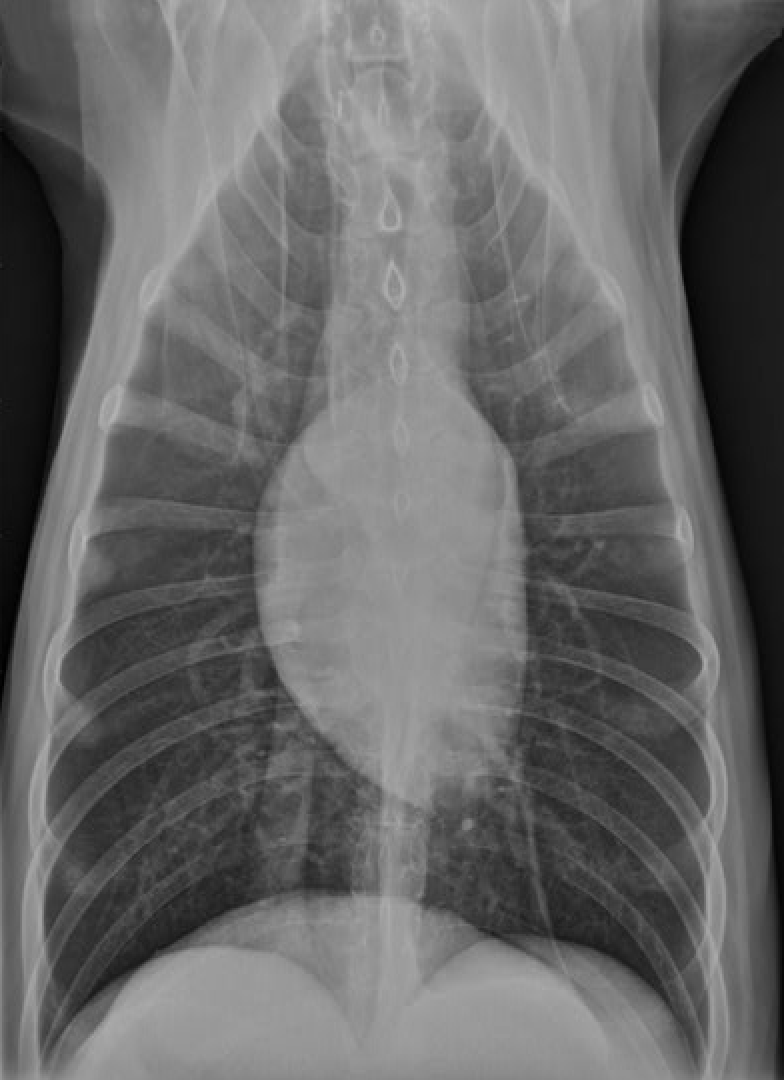

identify the structures

RA: right auricle (atrium)

RV: right ventricle

LV: left ventricle

LA: left atrium

A: aorta

C: caudal vena cava

T: trachea

Identify Manubrium of sternum, First rib, Apex of heart, Base of heart, Diaphragm and First lumbar vertebra

Again note the shape of thoracic cavity. How does it compare to that of the dog?

Narrower particularly about the thoracic inlet